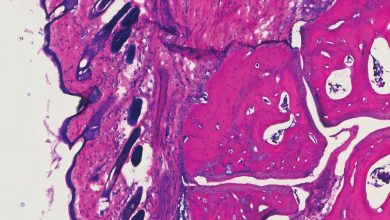

Histologia mostrando a articulação do tornozelo de um camundongo quatro dias após receber o novo tratamento com anticorpos, V11 sFc.…

Ler Mais » - Notícias